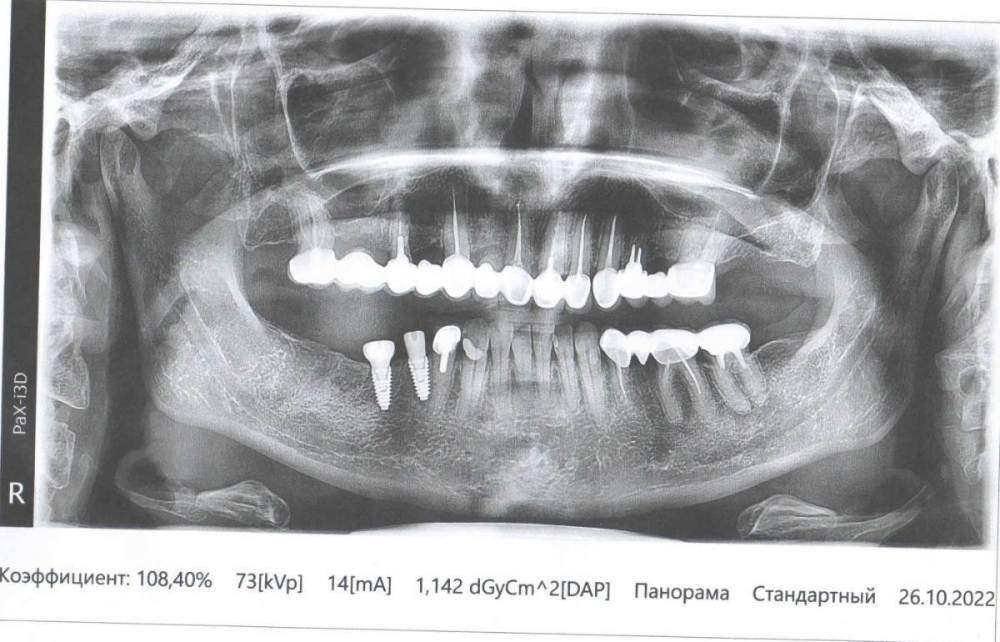

regina69 Опубликовано 27 октября, 2022 Поделиться Опубликовано 27 октября, 2022 Добрый день. Подскажите, пожалуйста, что можно сделать в моей ситуации. Установлены 2 импланта 11.08.22г. Перед этим хирург и ортопед долго не могли договориться о том куда ставить. Хирург хотела 46 и 47, а ортопед настоял на 45 и 46. В итоге уже 2,5 месяца тупые ноющие боли. При постукивании боли нет. Соблюдала все условия после операции, до сих пор не жую на этой стороне, только чищу мягкой щеткой. Ссылка на комментарий

chervoncevdaniil Опубликовано 27 октября, 2022 Поделиться Опубликовано 27 октября, 2022 Пусть вас посмотрит еще кто то из врачей очно,есть предположение,что имплант 45 поставлен очень близко к зубу 44. По этому двухмерному снимки точно сказать нельзя,нужен осмотр врача+дополнительные снимки. Если это так,то возможно это и являяется причиной ваших болей 1 Ссылка на комментарий